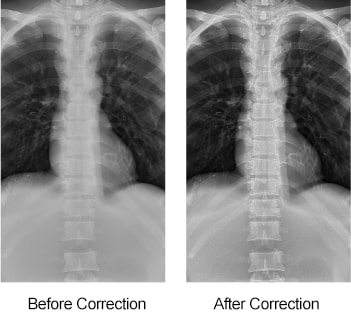

Scatter Correction OPTION

Reduces the effect of scattered radiation and enhances image contrast for grid-free examinations. Lowers the required dose by over 50 %. Reduces the risk of re-takes due to improper grid positioning.